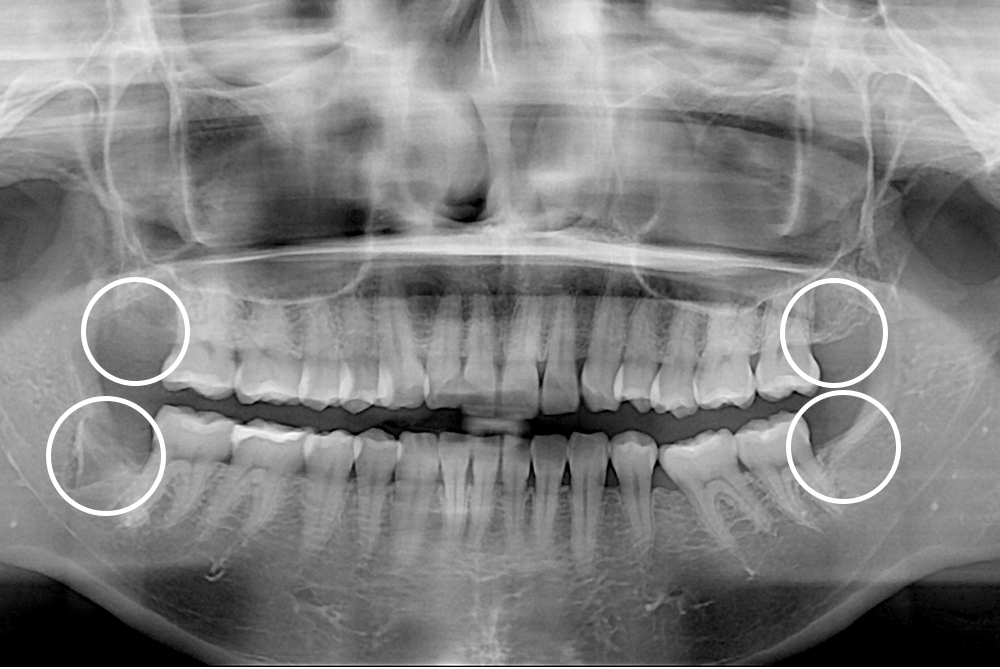

치료후 : 2021-03-22

세종치과는 구강악안면외과학 박사이신 원장님이 발치하는 치과입니다.